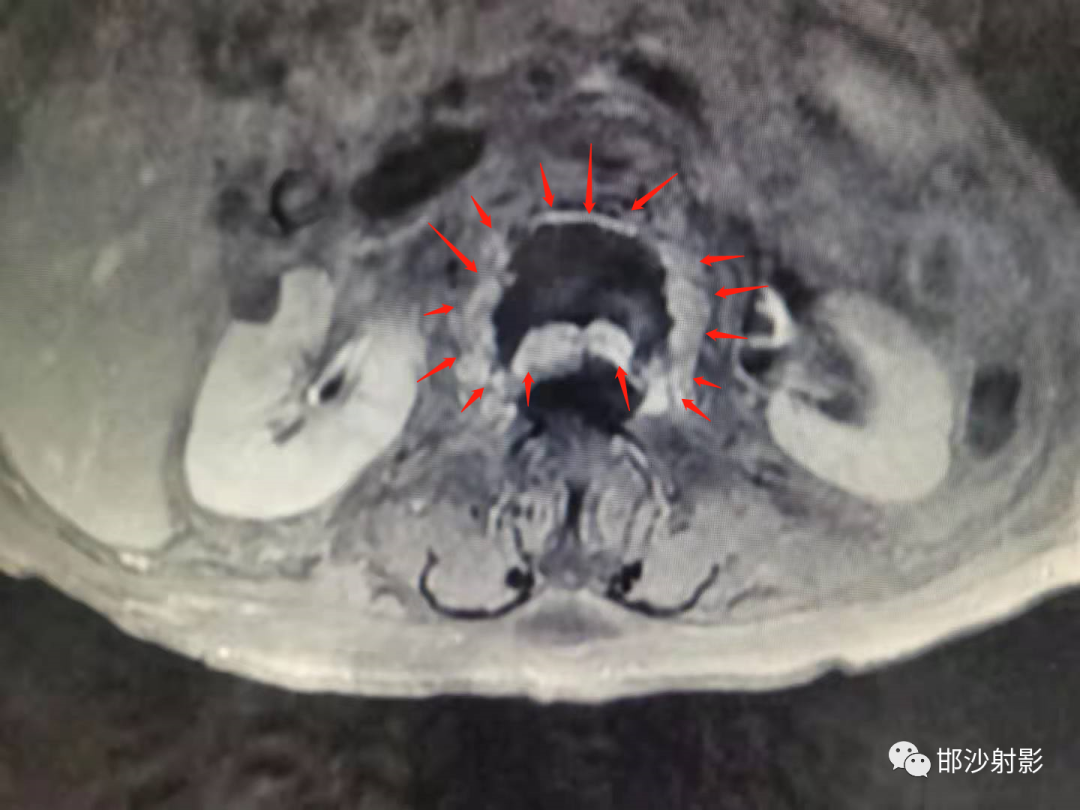

T1WI增强扫描:

红箭显示环形肉芽组织强化,呈蛋壳样分布;

MRI:可以有效评估。根据研究发现,MRI 及病理可将 IVC 表现分四型:①液体型,T1WI 低信号、T2WI 散在高信号, 病理学上为广泛的椎体坏死及坏 死后骨吸收;②压缩型,椎体明显楔形变(前柱明显变扁而后 柱无明显变化),T1WI 低信号,T2WI 中等信号,病理上为椎体 坏死、骨髓纤维化、肉芽及反应性新生骨形成;③肉芽组织 型,T1WI 低信号、T2WI 中等信号, 信号分布较压缩型更广且 椎体后部受累及, 病理学为广泛肉芽组织形成;④混合型, MRI 及病理学为前述各型的混合表现。